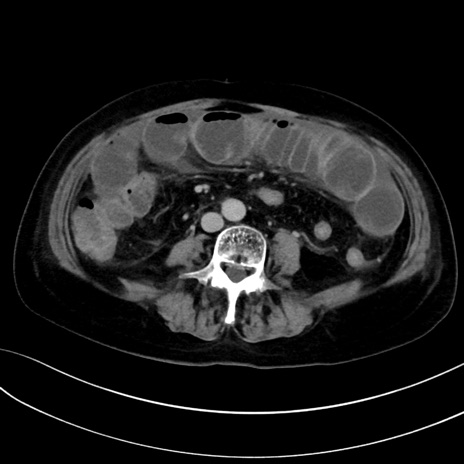

症例13 CT(横断像)1日半後